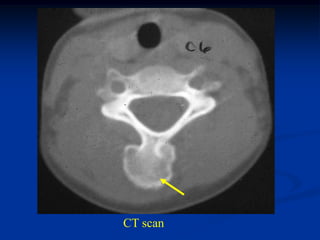

Case #574

2 year male

Ollier’s lower

extremity